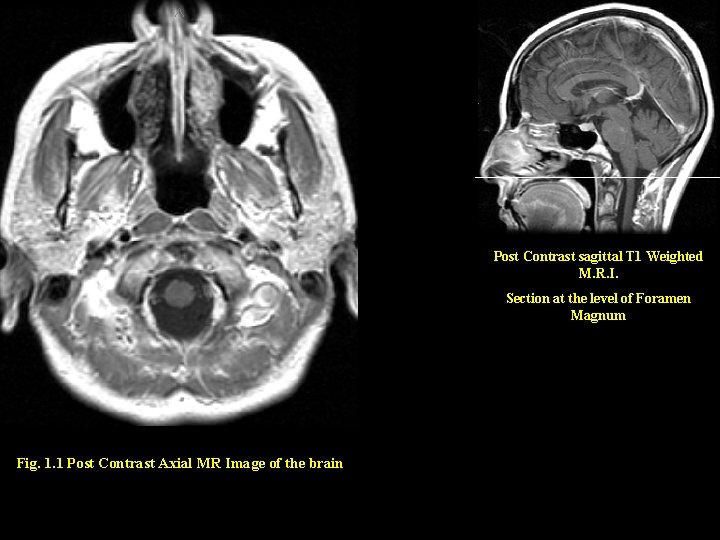

Post Contrast sagittal T 1 Weighted M. R. I. Section at the level of

Post Contrast sagittal T 1 Weighted M. R. I. Section at the level of Foramen Magnum Fig. 1. 1 Post Contrast Axial MR Image of the brain

5 3 Post Contrast sagittal T 1 Weighted M. R. I. 2 Section at the level of Foramen Magnum 1 Answers 4 1. Cisterna Magna 2. Cervical Cord 3. Nasopharynx Fig. 1. 1 Post Contrast Axial MR Image of the brain 4. Mandible 5. Maxillary Sinus